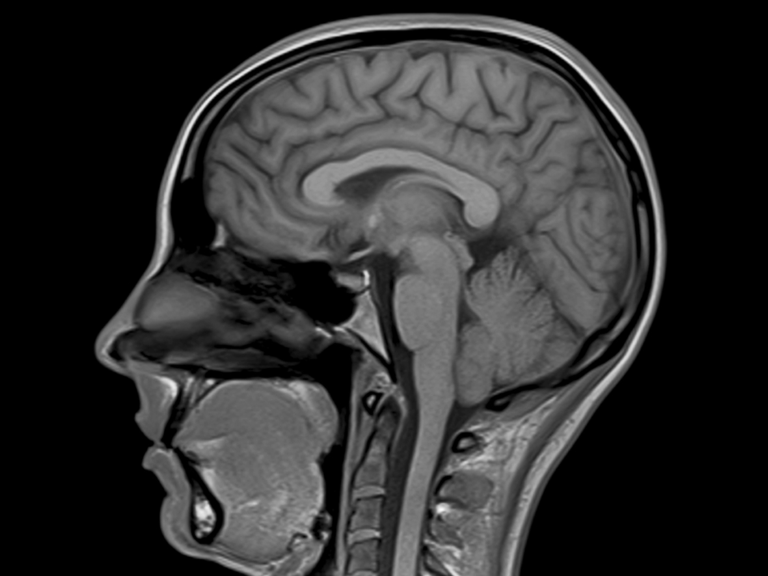

Mri Dye Dangers . the contrast material used in mri (magnetic resonance imaging) called gadolinium is less likely to produce an allergic reaction. risks and contraindications. for the majority of patients, the dye is believed to be safe. An mri with contrast is an imaging test that combines magnetic and radio wave imaging. But in the past few years, some patients have reported new, serious side effects that. Risk factor is acute or chronic renal failure. gadolinium contrast agents help improve the quality of mri scans. Side effects include nephrogenic systemic fibrosis (nsf) which is associated with the administration of intravenous gadolinium.